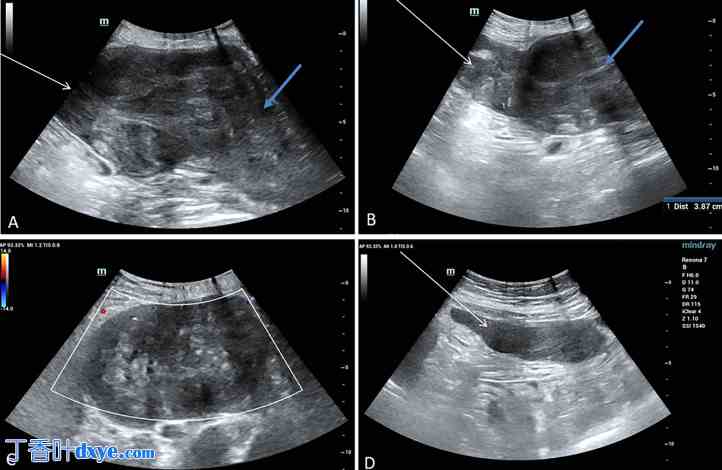

剖宫产术中发现子宫底肌层存在非典型肿块(图1)。由于该肿块具有非典型特征,故未行肌瘤切除术。术后超声检查显示子宫底肌瘤呈异质性,边界不规则,同时左侧髂窝壁下区可见回声相似的腹膜肿块(图2)。

图2.

超声图像。(A) 巨大的浆膜下平滑肌瘤(白色箭头)推移子宫(蓝色箭头)。该肌瘤与子宫底壁无法分离。 (B)浆膜下平滑肌瘤穿孔(蓝色箭头),形成4厘米的缺损,坏死物质流入腹腔(白色箭头)。(C)浆膜下肌瘤内部无血流信号,提示肉样变性。(D)腹腔内可见坏死物质(箭头)。